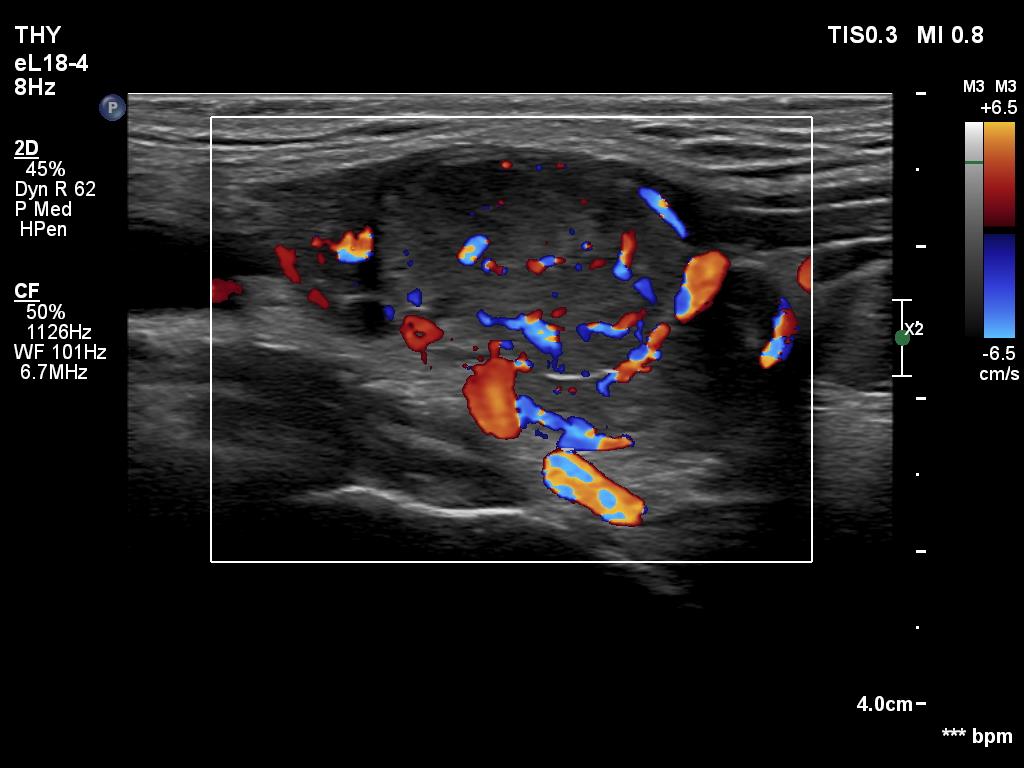

Ultrasonography. The thyroid was hypoechoic. The right lobe had a heterogeneous, dominantly minimally/moderately hypoechoic nodule in the ventrolateral part which had irregular borders and both perinodular and intranodular vascularity. There was another, hyperechoic star-like lesion in the central part of the right lobe. This lesion presented microcalcifications and was avascular. The left lobe was homogeneously hypoechoic.

According to the palpable mass in the right submandibular area, there was a heterogeneous lesion which has hypoechoic and echonormal parts. The mass had irregular margins and showed vascularity. The distance between the submandibular mass and the thyroid was more than 35 mm.